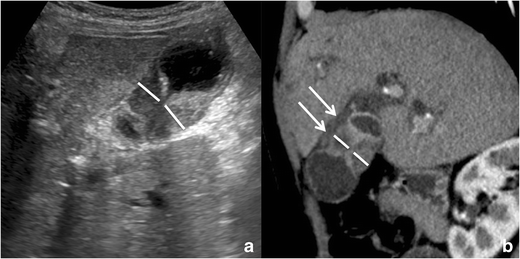

The finding of a gallbladder wall thickening at computed tomography (CT) may represent a diagnostic dilemma; in fact, unless clear signs of malignancy are present, CT has an unsatisfactory accuracy in their differential diagnosis. The accuracy of CT in differentiating GA from gallbladder carcinoma is between 40 and 75% [32] and a confident diagnosis of GA is possible only if large (at least 3–4 mm) RAS are present.

Imaging findings

Gallbladder wall thickening without extra-parietal growth can be confidently observed at CT, with sensitivity comparable to the other modalities.

Well-delimitated hypodense intramural spaces, representing RAS, can be confidently recognized only if they reach 3–4 mm in diameter and if they have a clear bile content (Fig. 13). If RAS are clearly identified, CT diagnosis of GA can be made.

Fig. 13

Gallbladder adenomyomatosis: typical CT findings. At CT, gallbladder adenomyomatosis is characterized by mural thickening (line) containing cystic spaces representing Rokitansky–Aschoff sinuses (arrows). Large RAS can be easily identified on 3-mm-thick reconstructions (a), whereas for identifying smaller RAS thin slices evaluation is crucial (b)

Bild vergrößern

Focal intramural calcifications (Fig. 14) are virtually pathognomonic for GA. Unfortunately, GA shows intramural calcifications only in a minority of the cases.

Fig. 14

CT of gallbladder adenomyomatosis: intramural calcifications. CT accurately depicts intramural calcifications (arrows) that may develop within Rokitansky–Aschoff sinuses and which are pathognomonic for gallbladder adenomyomatosis